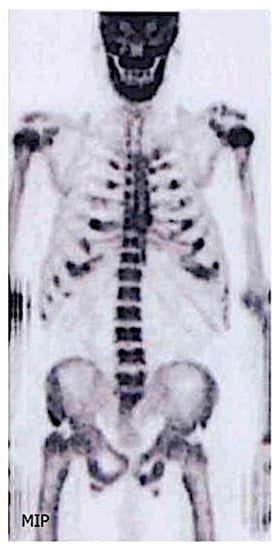

3.8. Other Imaging Techniques

- Abdelrazek, S.; Szumowski, P.; Rogowski, F.; Kociura-Sawicka, A.; Mojsak, M.; Szorc, M. Bone scan in metabolic bone diseases. Review. Nucl. Med. Rev. 2012, 15, 124–131. [Google Scholar]

- Aaltonen, L.; Koivuviita, N.; Seppänen, M.; Tong, X.; Kröger, H.; Löyttyniemi, E.; Metsärinne, K. Correlation between 18F-Sodium Fluoride positron emission tomography and bone histomorphometry in dialysis patients. Bone 2020, 134, 115267. [Google Scholar] [CrossRef] [PubMed]

- Messa, C.; Goodman, W.G.; Hoh, C.K.; Choi, Y.; Nissenson, A.R.; Salusky, I.B.; Phelps, M.E.; Hawkins, R.A. Bone metabolic activity measured with positron emission tomography and [18F]fluoride ion in renal osteodystrophy: Correlation with bone histomorphometry. J. Clin. Endocrinol. Metab. 1993, 77, 949–955. [Google Scholar] [CrossRef] [PubMed]

| Bone Scintigraphy | Tracer accumulation occurs in osteoblastic activity, and to a lesser extent, skeletal vascularity; Systemic amyloid burden; | Whole body | Osteoarthritis Metabolic Bone Disease: -Hyperparathyroidism and vitamin D deficiency -Osteomalacia; Fractures Enthesopathies Osteonecrosis Rare Osteoarticular Diseases: Sarcoidosis with bone involvement; Amyloidosis: 123I SAP scintigraphy if available—assess amyloid deposition in liver, spleen, kidneys, adrenals, localized soft tissue deposits and bones 131I-β2M amyloidosis | 3–5 |

| PET | Bone formation rate, osteoclast, osteoblast, erosion and mineralized surfaces | Lumbar region | Low or high bone turnover disease | All |